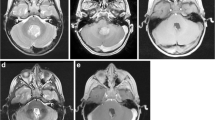

In preparation for a fifth attempt at local control, a neurosurgical iMRI (Siemens; Munich, Germany; 1.5 Tesla magnet on mobile track) was modified to perform an iMRI-assisted sarcoma resection of the lower extremity recurrence areas. Partnering with hospital staff engineers, the operating table was modified, following blueprint designs, using MRI-compatible materials (ie, brass or plastic polymer screws and washers, plastic or carbon fiber platform) to accommodate patient positioning that would allow for adequate observation of the musculoskeletal field (proximal leg, pelvis) in the mobile iMRI scanner (Fig. 1). After immediate preoperative contrast MR images were obtained for comparison purposes, the patient was brought to the iMRI surgical suite and positioned on the modified iMRI table. Using primarily short Tau inversion recovery (STIR) axial sequencing cuts, the anterior tumor and medial tumor recurrence locations (Fig. 2) were confirmed before incision, by comparing immediate preoperative images with the same intraoperative STIR sequences. After identifying the tumor location following initial dissection, the surgical field was imaged a second time to determine an appropriate resection margin surrounding each recurrence (Fig. 3). After tumor excision, both specimens were removed from the surgical field, but kept in the iMRI scanning field (Fig. 4). A third scan then was done to confirm adequate resection of the field and to confirm the specimen with appropriate tissue margins. Through intraoperative frozen section assessment and postoperative permanent section review, the two specimens were confirmed histologically to have negative margins. No contrast was used for reasons described by Gould et al. [9], detailed in the Discussion. To date, the patient has no evidence of disease at 37 months after MRI-assisted resection.

In our modified operative suite, (A) the table extension (to accommodate the extremity) is made of nonmagnetic objects, such as brass, polymers, and plastics. This modification can be removed easily and does not effect the use for future neurosurgery cases. (B) A technician attaches the table modification that allows the patient’s thigh or pelvis to enter the MRI scanner, with the patient in the supine position on the (C) modified table. (D) The MRI scanner is in a room adjacent to the operating room, and is moved to the operating room on (E) ceiling tracks thru a connecting door, with (F) all personnel, instruments, and equipment placed outside the gray peripheral line (magnetic field range) on the floor. An instrument count is performed before moving the instruments out of the magnetic field (any instrument unaccounted for is a potential projectile), while positive pressure flow prevents dirty airflow into the operating room suite while the magnet moves into position. (G) The scanner moves over the table extension, (H) encircling the extension where the operative extremity is positioned. With each MRI scan the machine takes 15 minutes to move along the tracks (and a reciprocal 15 minutes to exit the room), with 10 to 15 minutes used to count instruments with each cycle. In this case, we performed three separate image acquisitions, taking approximately 45 minutes for each cycle, accounting for 135 minutes of operating room time. In addition, the image acquisition and interpretation took approximately 15 minutes each time. Use of MRI for resection guidance accounted for nearly 3 hours of additional operative time.